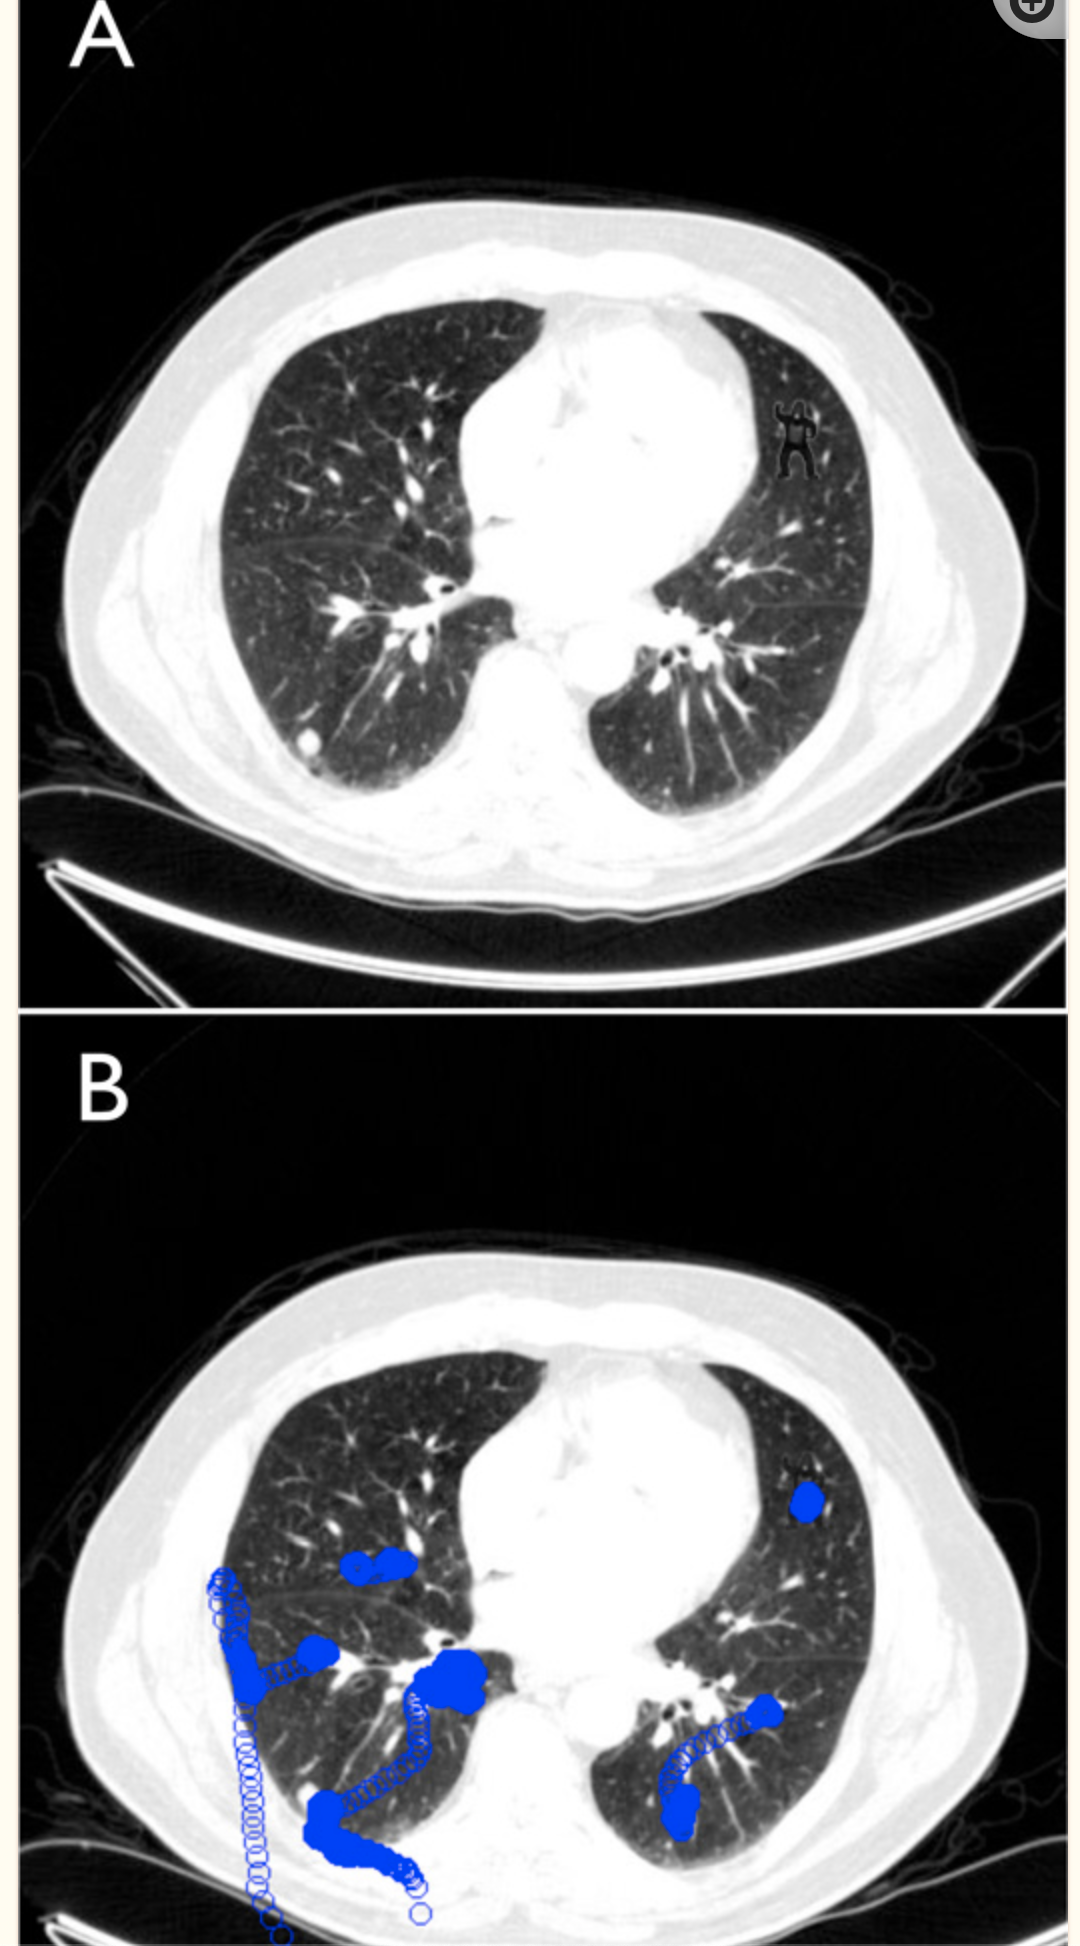

A seminal radiology study in 2013 played a significant role in shaping the discourse on automation in medicine. In this study, twenty-four radiologists participated in a familiar lung nodule detection task. Researchers surreptitiously inserted the image of a gorilla, forty-eight times larger than the average nodule, into one of the cases. The findings were astonishing: 83 percent of radiologists failed to see the gorilla, even though eye-tracking data showed that most were looking directly at it. In the images below, you should be able to spot a gorilla (hint: look in the top right portion of the lung image).